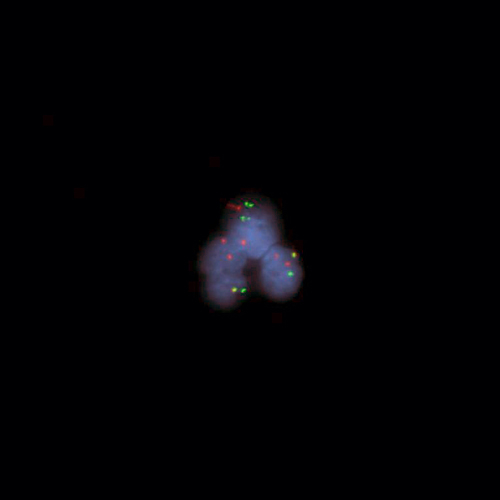

Kreatech FISH probes are the latest in advancements in FISH probes. Developed with the use of REPEAT-FREE technology, Kreatech FISH probes eliminate the use of Cot-1 or blocking DNA, providing a clearer background and a brighter signal.

Novocastra FISH Probes

Reliably detect RNA sequences with Novocastra ISH probes, detection systems, and ancillary reagents.